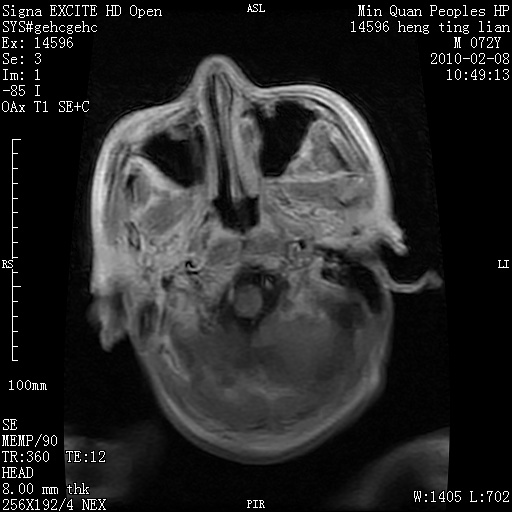

m,72,头疼,头晕两年,伴视力模糊三月,饮食呛咳两天。pe:颈部抵抗,左眼突出,左眼瞳孔约3mm,对光反射消失,双眼失明,伸舌困难,双肺呼吸音粗,心率110次/分,左上肢肌力i级,左下肢屈曲,肌张力高。现有08年2月19mri平扫及10年2月8日mri增强请会诊。ct病灶呈低密度伴散在点、片状等密度区,无明确钙化(无ct片资料可供上传)。[

脑外肿瘤,囊实性,环状不规则强化,内听道扩大,考虑神经源性肿瘤

左侧桥小脑区占位伴梗阻性脑积水----考虑 1神经鞘瘤 2室管膜瘤。

左侧桥小脑区神经鞘瘤伴梗阻性脑积水。

脑外肿瘤,病灶呈匍匐蔓延,表皮样囊肿可能性大。